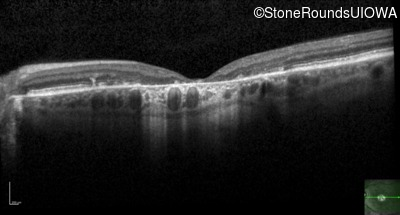

AR Stargardt Disease (IIA)

Age at visit: 52 years

This 52 year old man first noticed reduced visual acuity at age 21.

Diagnosis & molecular findings

AR Stargardt Disease ABCA4 Glu471Lys GAA>AAA / Glu2131Lys GAA>AAA Asp2181 del36gaCCTGAACCCTGTGGAGCAGTTCTTCCAGGGGAACTT AR